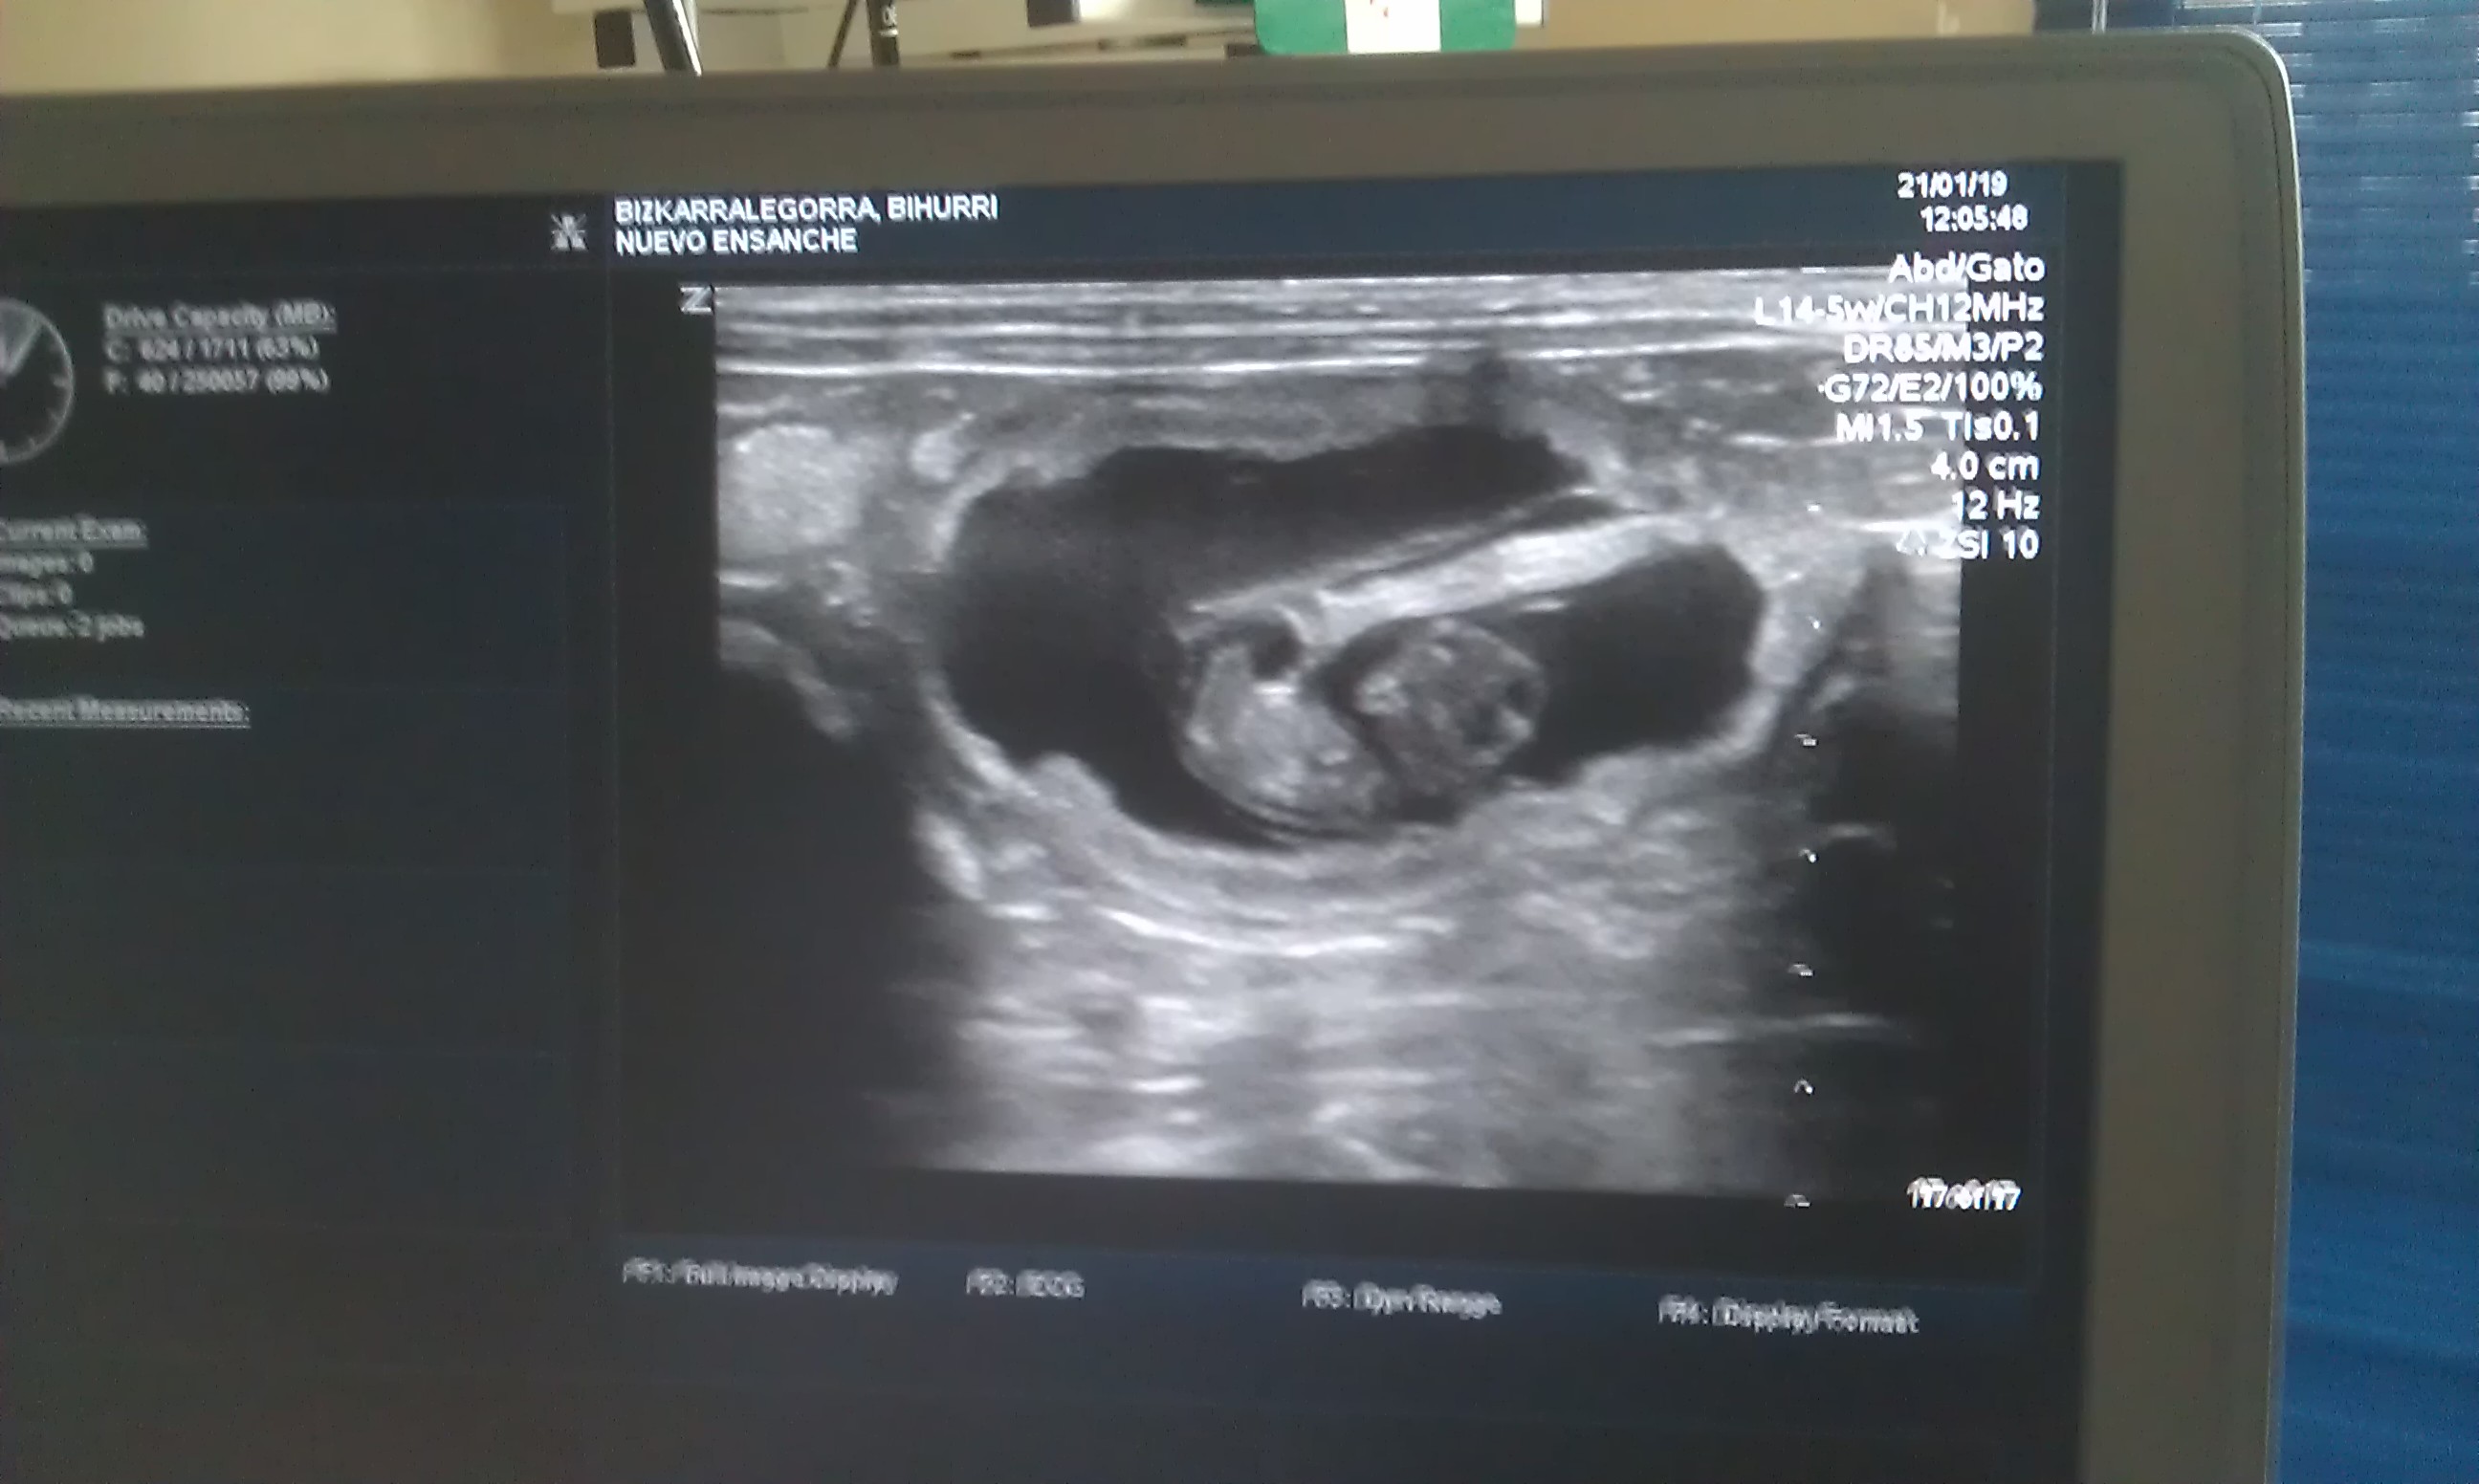

Día de gestación 23

L. 21-1-2019

Las ecografías confirman que 4 crías están en camino.

Bihurri (2d), cría-9a

Bihurri (2d), cría-9b